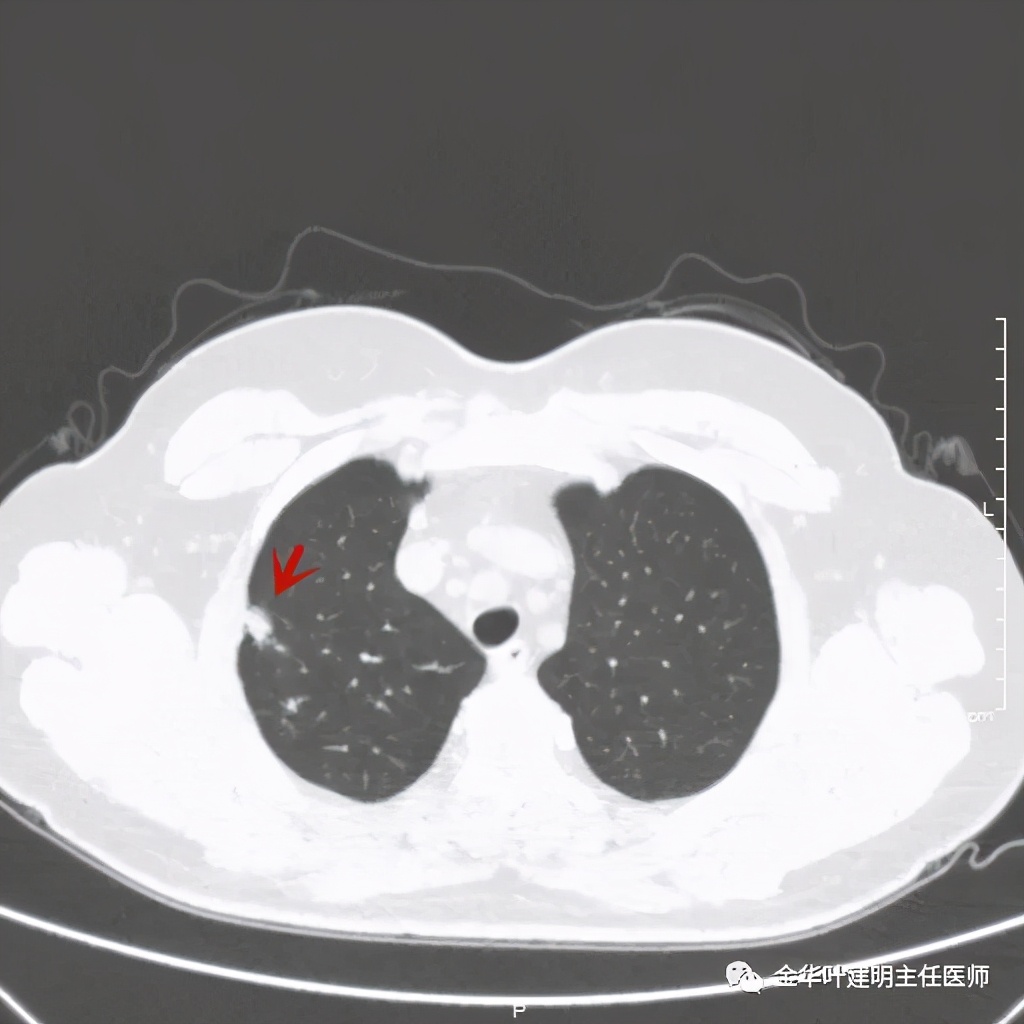

今天分享一个病例,不是我自己的病人,是个36岁的女性,检查发现右上叶占位。肿瘤筛查指标正常。先来看其CT片的肺窗:

右上叶开始出现病灶,是实性的